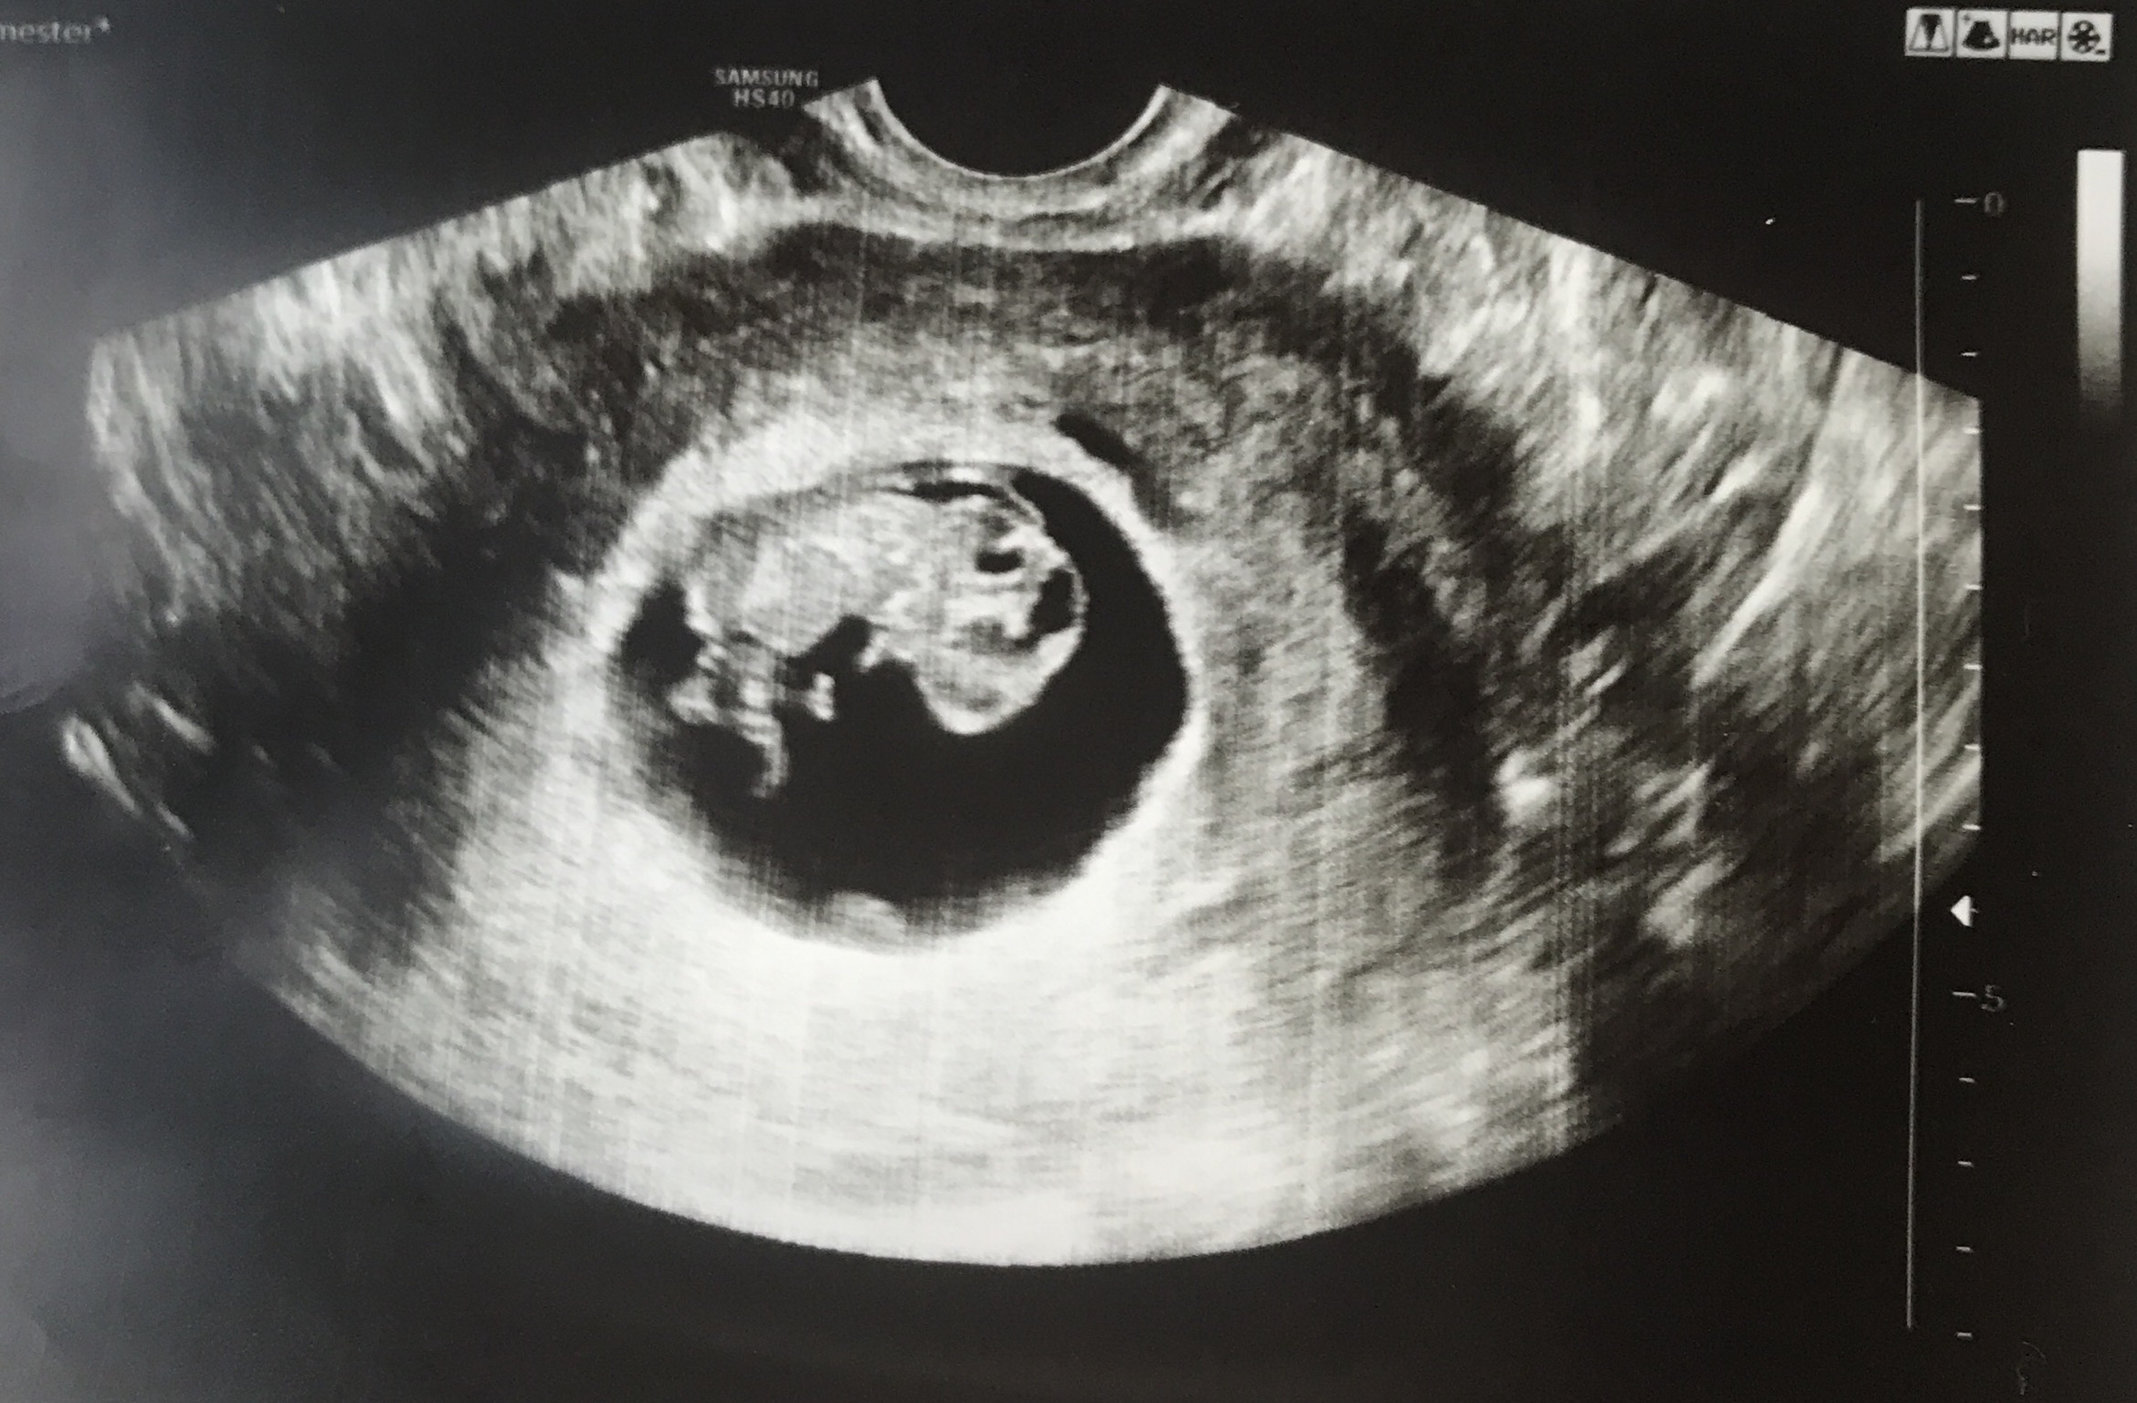

This pic was on Thursday at 13weeks2days. Can’t believe we are almost in our second trimester! She was moving around and bobbing her head. Love seeing her so active